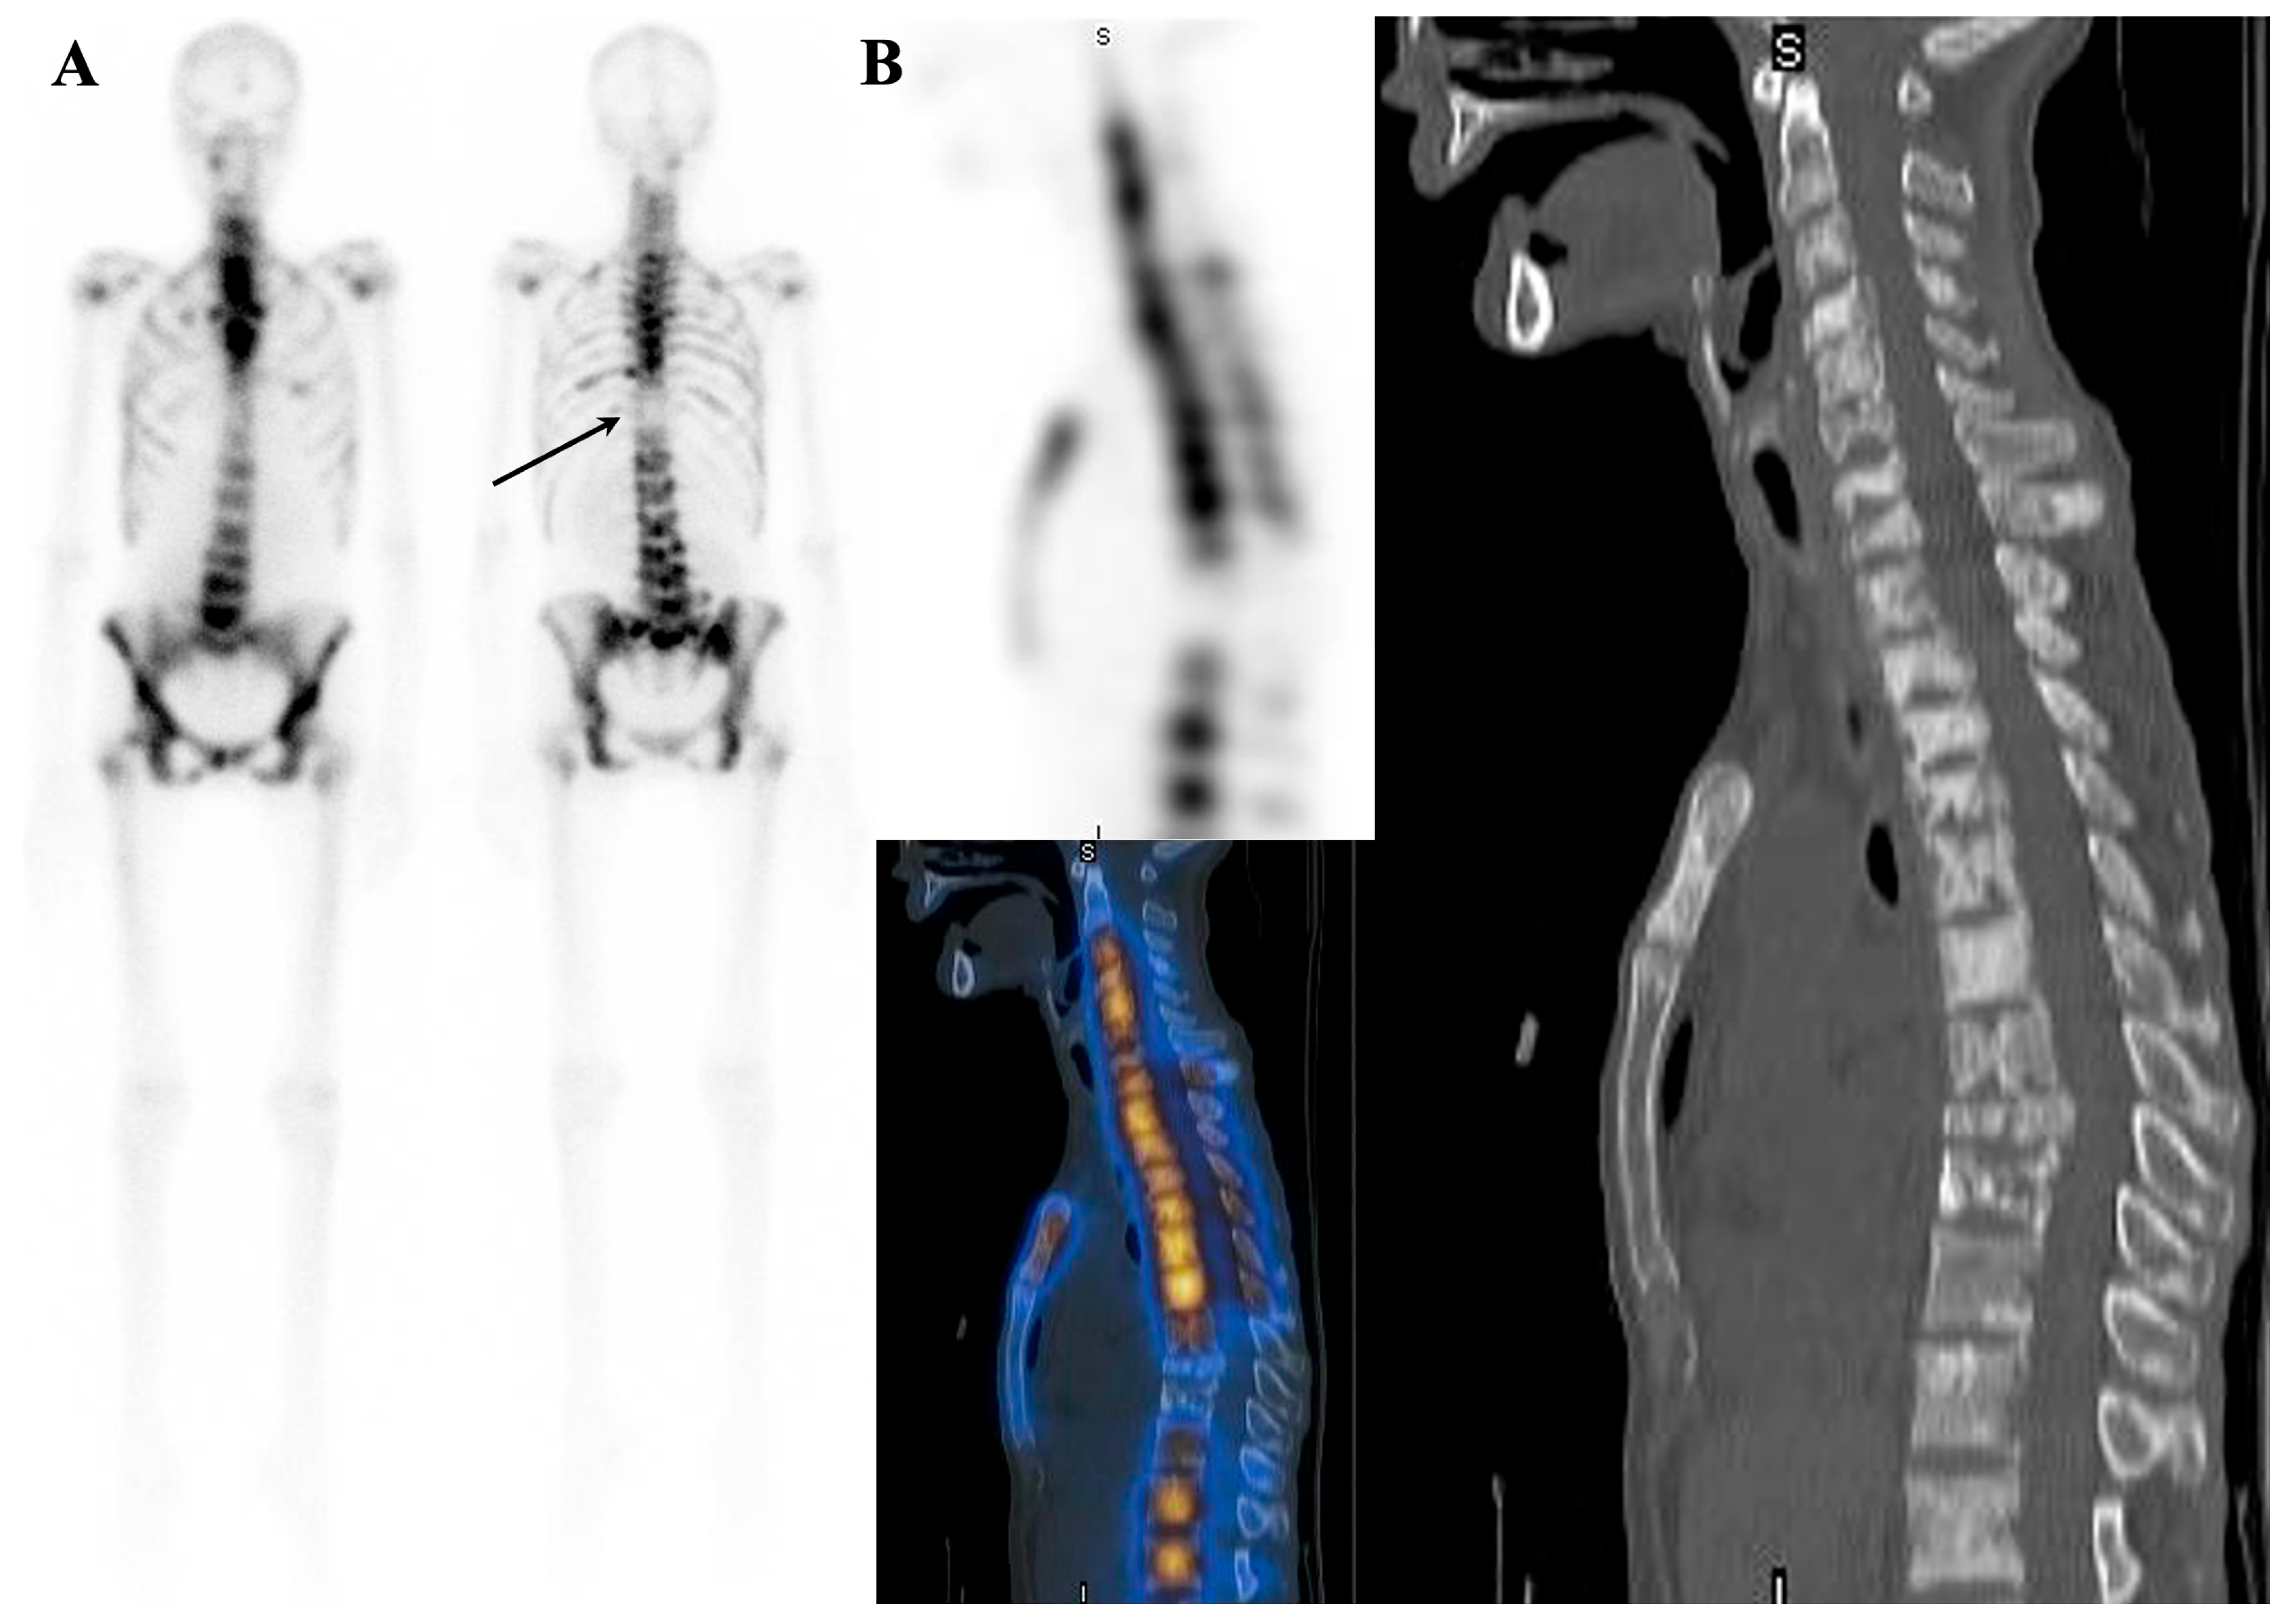

7.1. Metastatic Superscan

7.1.1. Superscan Pattern in Patients with Prostate Cancer

7.1.2. Dynamic Changes in Prostate Cancer Patients with Superscan

7.2. Metabolic Superscan